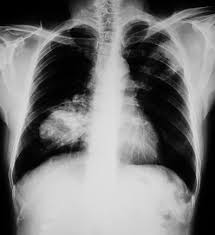

Early Signs Of Lung Cancer On Ct Scan - Google Says Its Ai Could Detect Early Signs Of Cancer Cnet : Lung nodules are tiny collections of tissue that appear in the lungs.. The larger nodules are more likely to be cancerous. How a ct scan works However, it can occur in other heart and lung diseases. Because many cases of lung cancer are not diagnosed early, as a first step in early detection, it is important to familiarize yourself with some of the early symptoms of the disease, which can include: Ct (or cat) stands for computed (axial) tomography.

One of the first signs of lung cancer that usually people tend to dismiss is a new cough that tends to persist. The ct scan might show signs of cancer, but that cancer might not be active for example, it could be scar tissue left over from cancer killed off by your treatment While it might seem obvious to assume that finding small tumors reduces one's likelihood of dying from lung cancer, this is incorrect. These small differences in lung nodules show on ct scans and can indicate if a nodule is cancerous or not. Changes in breathing can occur if lung cancer blocks or narrows an airway, or if fluid from a lung tumor.

One of the first signs of lung cancer that usually people tend to dismiss is a new cough that tends to persist. Changes in breathing can occur if lung cancer blocks or narrows an airway, or if fluid from a lung tumor. This mass will look like a white spot on. A persistent cough not related to an illness. Ct (or cat) stands for computed (axial) tomography. As reviewed by bram van ginneken, phd, of the radboud university medical center in the netherlands, quantitative measures obtained from a chest ct scan may enable the early detection of different obstructive and interstitial lung diseases, such as chronic obstructive. Shortness of breath or becoming easily winded are also possible symptoms of lung cancer. The term tomography comes from the greek words tomos (a cut, a slice, or a section) and graphein (to write or record). The mayo clinic lists some of the common symptoms of lung cancer, which range from general hoarseness to coughing up blood. Each picture created during a ct procedure. When people experience signs and symptoms of lung cancer, the early ones may include any of the following: However, if it is an early warning sign of lung cancer, then this persistent cough will tend to linger. Without screening, 70 percent of lung cancers are found at a later stage when there is little chance for a cure.

Each picture created during a ct procedure. The main benefit of lung cancer screening is preventing death from lung cancer. Lung nodules are tiny collections of tissue that appear in the lungs. Lung cancer screening finds 80 percent of lung cancer at an early stage when it is more curable. Lung cancer can sometimes be detected in its early stages with a lung scan.

Researchers Using Artificial Intelligence To Detect Early Signs Of Lung Pancreatic Cancers Abc7 Los Angeles from cdn.abcotvs.com Patients with lung cancer may be asymptomatic in up to 50% of cases. Early detection is the key. Ct scan for lung cancer. The mayo clinic lists some of the common symptoms of lung cancer, which range from general hoarseness to coughing up blood. Changes in breathing can occur if lung cancer blocks or narrows an airway, or if fluid from a lung tumor. When people experience signs and symptoms of lung cancer, the early ones may include any of the following: It is used to look for early signs of lung cancer. Pneumonia, pleural effusion, wheeze, lymphadenopathy are not uncommon.

Patients with lung cancer may be asymptomatic in up to 50% of cases. Around 40 percent of lung nodules are cancerous (malignant). They appear due to scarring caused by a previous infection or a benign tumor. If the test finds cancer, treatment can start early. Each picture created during a ct procedure. It is sometimes called computerized tomography or computerized axial tomography (cat). Ldct scans can help find abnormal areas in the lungs that may be cancer. Find out if you are eligible for the early lung cancer detection program. The term tomography comes from the greek words tomos (a cut, a slice, or a section) and graphein (to write or record). Ct scans are inaccurate for treatment monitoring after cancer treatment, a ct scan is unable to determine whether masses leftover are cancerous: It is detectable by early symptoms such as constant coughing, chest pain, and many more. While it might seem obvious to assume that finding small tumors reduces one's likelihood of dying from lung cancer, this is incorrect. So what does a lung ct scan show?

Ct screening for lung cancer can reveal subtle early signs of disease in the lungs that extend beyond potential malignancy. Shortness of breath or becoming easily winded are also possible symptoms of lung cancer. Most doctors do not recommend pet/ct scans for routine follow up of patients after lung cancer treatment. The mayo clinic lists some of the common symptoms of lung cancer, which range from general hoarseness to coughing up blood. It takes pictures from different angles. a ct scan is needed if there is any concern. Lung nodules are tiny collections of tissue that appear in the lungs. Find out if you are eligible for the early lung cancer detection program. Pneumonia, pleural effusion, wheeze, lymphadenopathy are not uncommon. A persistent cough not related to an illness. Ct scans can detect cancer at a very small size. Patients with lung cancer may be asymptomatic in up to 50% of cases. It is used to look for early signs of lung cancer.